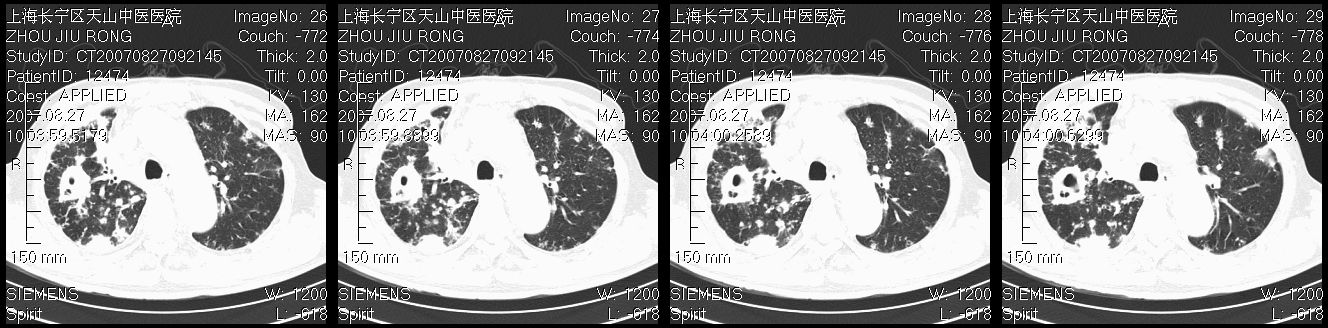

以下是引用zjzjr在2007-8-30 21:47:00的发言:[br]双肺弥漫性结节状、斑片状影,部分形成空洞,病灶以双肺上叶为著(符合结核发病部位),纵隔内见肿大淋巴结影。支持双肺继发性结核伴右上肺空洞形成。

以下是引用zjzjr在2007-8-30 21:47:00的发言:[br]双肺弥漫性结节状、斑片状影,部分形成空洞,病灶以双肺上叶为著(符合结核发病部位),纵隔内见肿大淋巴结影。支持双肺继发性结核伴右上肺空洞形成。

以下是引用gaoshengjiang在2007-8-31 10:24:00的发言:[br]双肺弥漫性斑片状影及多发空洞影,其间夹杂多量条索状影,胸膜肥厚、粘连并有结节状改变,纵隔多枚淋巴结肿大,考虑1双肺继发型肺结核合并感染?2韦格氏肉芽肿?[br] 支持!

以下是引用zjzjr在2007-8-30 21:47:00的发言:[br]双肺弥漫性结节状、斑片状影,部分形成空洞,病灶以双肺上叶为著(符合结核发病部位),纵隔内见肿大淋巴结影。支持双肺继发性结核伴右上肺空洞形成。

以下是引用zjzjr在2007-8-30 21:47:00的发言:[br]双肺弥漫性结节状、斑片状影,部分形成空洞,病灶以双肺上叶为著(符合结核发病部位),纵隔内见肿大淋巴结影。支持双肺继发性结核伴右上肺空洞形成。

以下是引用zjzjr在2007-8-30 21:47:00的发言:[br]双肺弥漫性结节状、斑片状影,部分形成空洞,病灶以双肺上叶为著(符合结核发病部位),纵隔内见肿大淋巴结影。支持双肺继发性结核伴右上肺空洞形成。